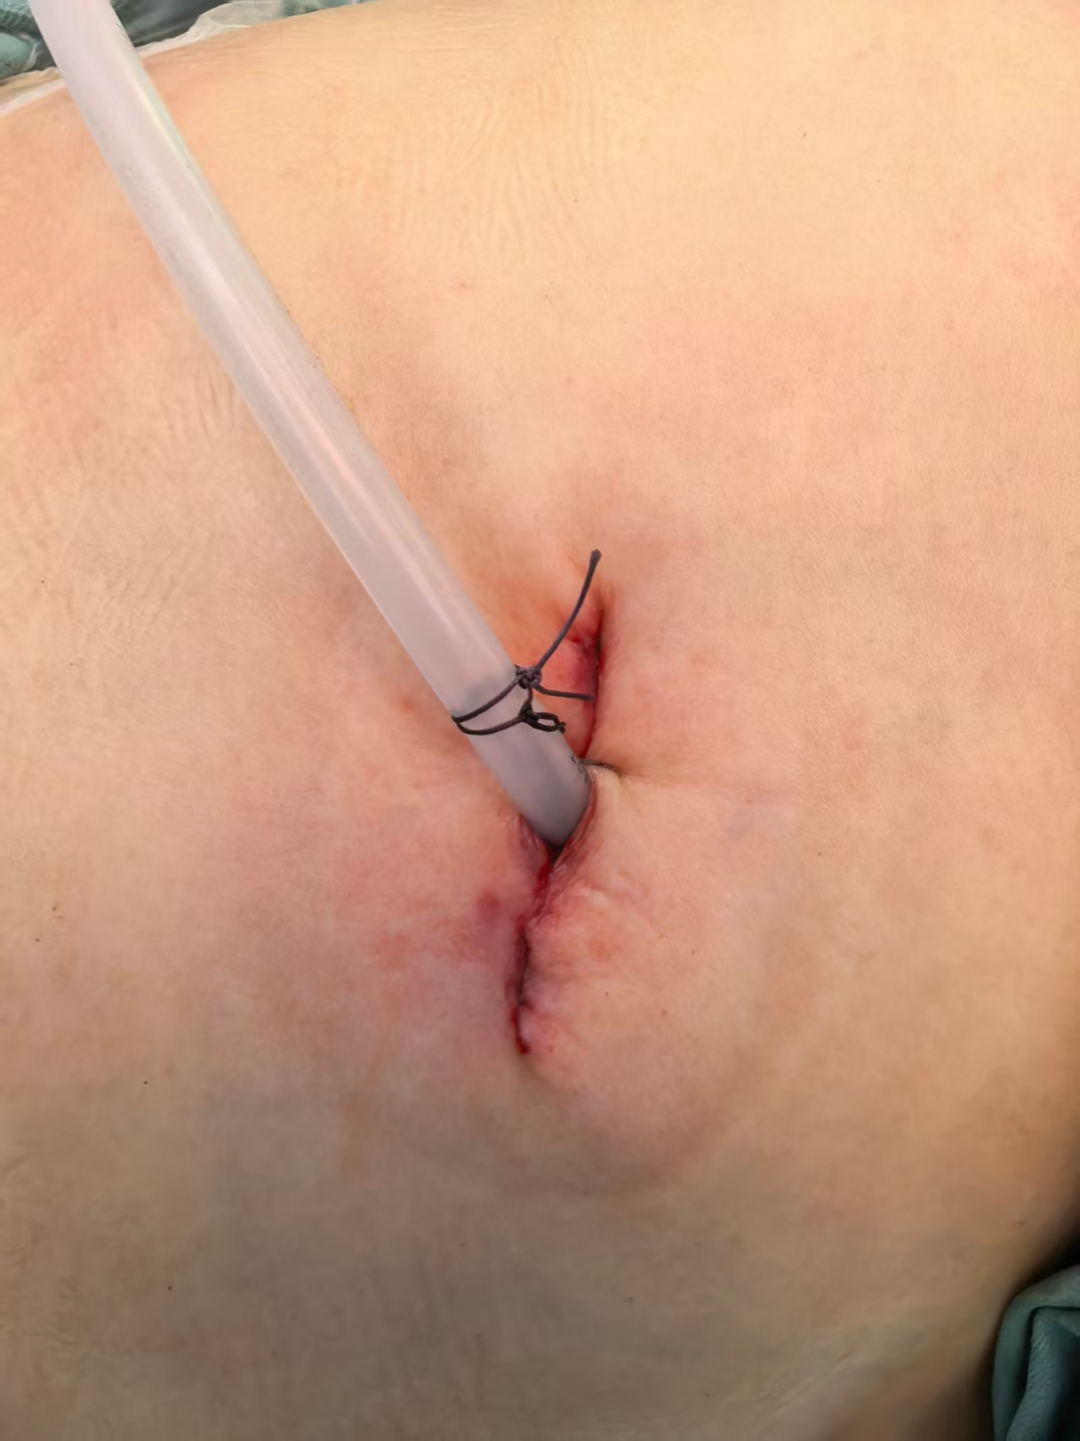

在术前,医疗团队运用 CT 引导技术,对结节进行了精准定位,为手术的顺利开展奠定了坚实基础。术中,结合三维重建技术,医生成功实施了精准肺联合亚段切除手术。整个手术过程仅耗时 1 个半小时,便顺利完成,充分展现了医疗团队的精湛技术与先进设备的完美结合。

术后,患者接受了快速康复治疗方案。在医护人员的精心照料下,患者恢复良好,仅术后 5 天便痊愈出院。经过我院的系统治疗,患者不仅身体得以康复,生活质量也得到了显著提升,重新拥抱健康美好的生活。